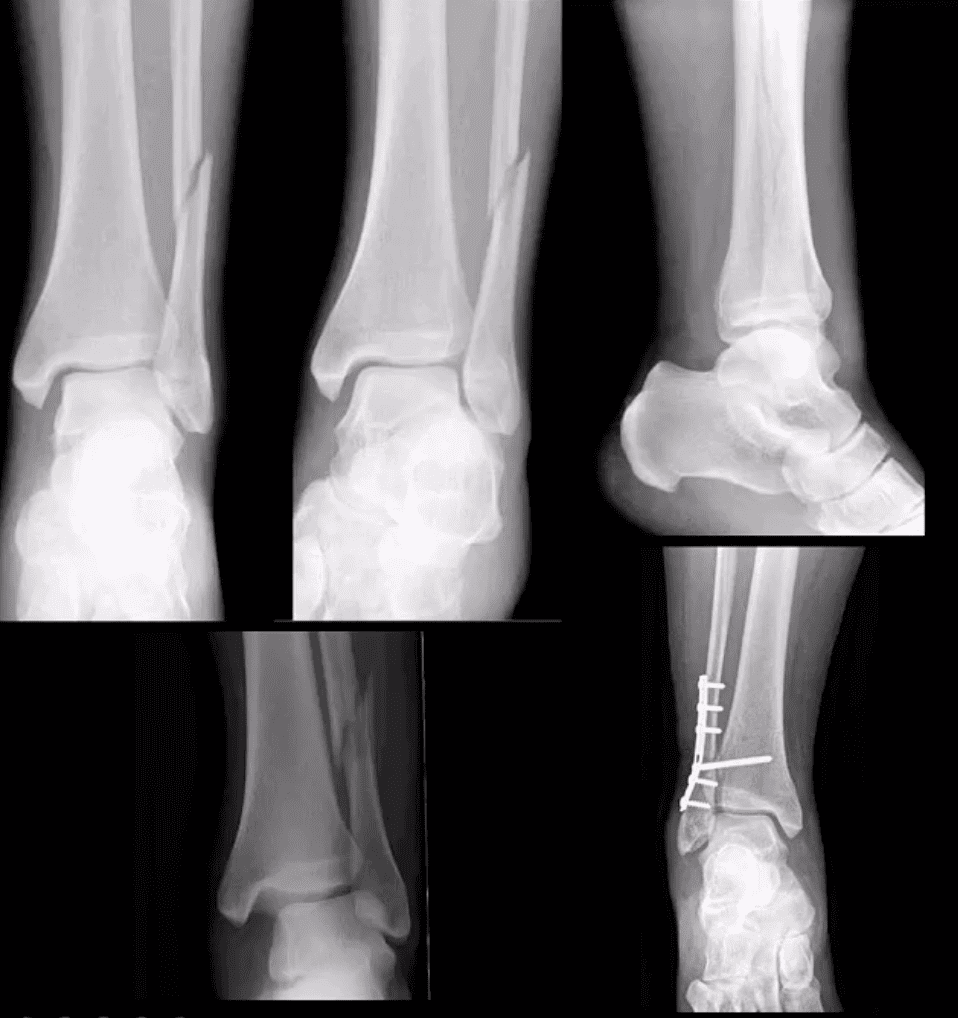

Weber C

- AP, medial oblique and lateral views reveal Weber C – suprasyndesmotic injury with abnormal joint widening d/t disruption of tib-fib syndesmosis. Very unstable injury.

- Occasionally, when Weber C Fx positioned 6-cm from the tip of the lateral malleolus it may be termed as Pott’s ankle Fx (name after Percival Pott’s who has porposed the original classification of ankle fractures based on their stability and degree of rotation). The term is somewhat outdated.

- Management: operative with additional stabilization of the syndesmosis

Maisonneuve Fracture

- Often spiral fracture of the proximal fibula combined with an unstable ankle injury

- No immediate ankle fracture is noted radiographically, thus can be missed on ankle views and require tibia and fibula views

- Rad features: widening of the ankle d/t syndesmosis tear and sometimes deltoid ligament disruption. Interosseous membrane is torn with proximal fibular Fx caused by pronation with external-rotation force

- Management: operative